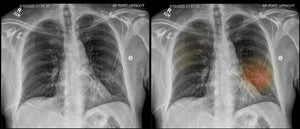

¿Qué pasa en los pulmones cuando hay infección por COVID-19?

¿Qué pasa en los pulmones cuando hay infección por COVID-19? Pese a que han pasado varios meses desde la aparición del coronavirus en el mundo, aún tenemos mucho que aprender acerca de él y de las secuelas que deja en el organismo, incluida la forma en que afecta los pulmones.Sabemos que el COVID-19 es una enfermedad de las vías respiratorias superiores y que las personas infectadas pueden propagar fácilmente al respirar, hablar o toser cerca de otra persona, incluso si no saben que lo tienen. Por ello, todos deberíamos distanciarnos socialmente y usar cubrebocas fuera de nuestra casa.“Después de entrar...